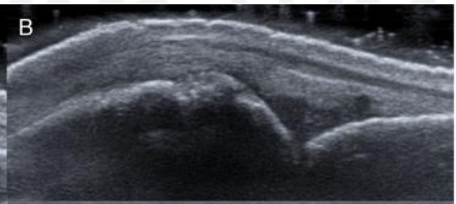

Grade The Synovial Hypertrophy

Grade this

B: grade 1 (up to 3 single signals — 1 confluent + 2 single — 2 confluent)

Minimal synovial hypertrophy up to the imaginary horizontal line connecting 2 joints; Power Doppler up to 3 single signals — 1 confluent + 2 single — 2 confluent

Grade 1: minimal

Moderate synovial hypertrophy protruding over the joint line along with concave surface; Larger than grade 1 but <50% of synovial hypertrophy covered by signals

Grade 2: moderate

Severe synovial hypertrophy producing beyond the joint line with convex surface; more than 50% of SH area covered by signals

Grade 3: Severe